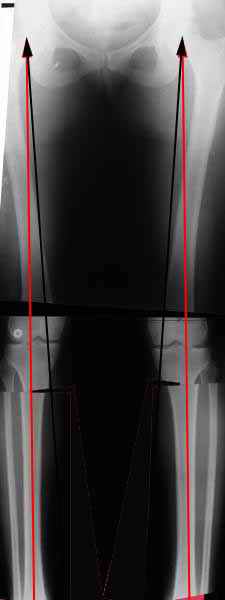

Вот, с учетом и без учета, и на разных уровнях...

Из приведнной схемы не совсеим понял что означают разноцветные линии.

И зачем латерализация периферического фрагмента. Я всегда делаю медиализацию. См схему. И для данного случая медиализация подходит как нельзя лучше.

a> Из приведнной схемы не совсеим понял что означают разноцветные линии.

Черные - это нынешняя механическая ось. Красные - это планируемая правильная ось.

a> И зачем латерализация периферического фрагмента.

;-) Читайте Палея. Стр. 114-115.

a> Я всегда делаю медиализацию. См схему. И для данного случая

Медиализация - это чисто эстетический прием, как я понимаю. Поскольку если делать остеотомию ниже вершины деформации, для восстановления оси надо делать смещение по ширине, в данном случае как раз латерализацию.